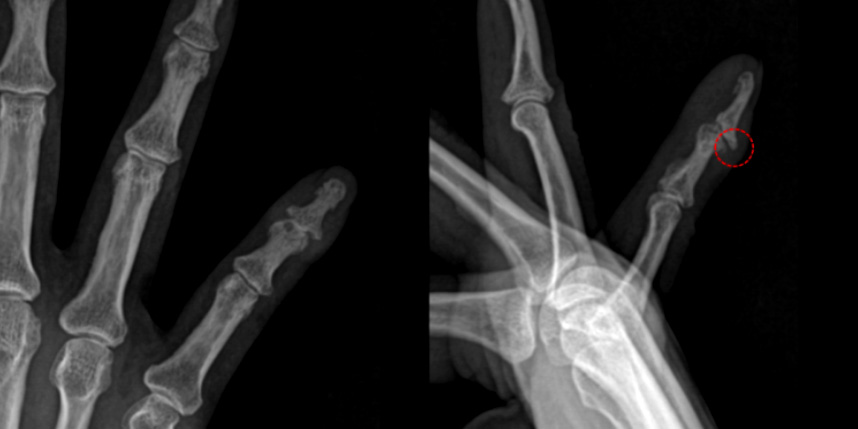

관절 유합술의 경우 증상이 심한 중증 관절염이 대상이 되며, 관절을 영구적으로 굳히는 수술이기 때문에

통증은 사라지고 휘어졌던 손가락이 일자가 되지만 끝마디 굴곡이 불가능해집니다. 직업적인 필요에 따라 굽힌 상태로 굳힐 수도 있으나

원위지절의 경우 일반적으로 완전히 편 상태로 굳히게 됩니다. 사람마다 차이가 있으나 한, 두 손가락에 하는 경우

굳어 있는 것에 대한 불편감보다는 통증 완화로 인한 만족감이 훨씬 높습니다.